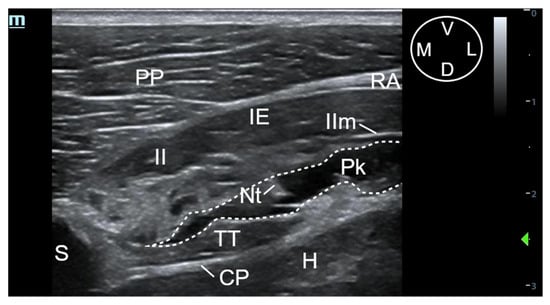

2.3.1. Ultrasound-Guided t-TTP Injection

Each cadaver was positioned in dorsal recumbence with the anterior limbs oriented cranially. The linear ultrasound transducer was positioned in a parasternal position slightly lateral to the fifth sternebra, between the fifth and sixth costal cartilage and parallel to the longitudinal axis of both costal cartilages with the marker oriented medially (Figure 1). The following thoracic structures were identified: pectoralis profunda, rectus abdominis and external and internal intercostal muscles, internal intercostal membrane, fifth sternebra, internal thoracic artery and vein, transversus thoracis muscle and costal pleura (Figure 2).

A 63 mm, 22-gauge spinal needle (BD Spinal Needle; BD Medical, Franklin Lakes, NJ, USA) was inserted in a ventromedial-to-dorsolateral direction with an in-plane technique. The needle was advanced through the pectoralis profunda, rectus abdominis, external and internal intercostal muscles, and internal intercostal membrane until the tip was positioned into the TTP, ventral to TT muscle and laterally to the internal thoracic artery and vein (Figure 2 and Figure 3). To confirm the presence of the needle tip into the target plane, a small amount of the injectable solution was slowly administered until a small pocket of fluid was visualized between the internal intercostal membrane and the transversus thoracis muscle. Then, the remaining volume corresponding to that side of the thorax was injected (Figure 3). If the solution injection did not reach the target plane, the tip of the needle was redirected and all the procedure was repeated. In all the injections, the quality of the needle tip ultrasound visualization was evaluated (Appendix A). The procedure was repeated on the contralateral side.

3.1.2. Description of the Sonoanatomy

The fifth sternebra was visualised as a triangular-shaped structure with a hyperechoic surface and acoustic shadow underneath. The pectoralis profunda muscle was visualised as a thick structure ventral and lateral to the sternum, separated from it and from the intercostal muscles by the rectus abdominis muscle, which appeared as a hypoechoic muscle with a thin and hyperechoic parasternal aponeurosis. The external intercostal muscle covers the lateral aspect of the internal intercostal muscle except for its most distal portion close to the sternum, where contacts laterally with the aponeurosis of the rectus abdominis muscle. The internal intercostal muscle extends distally until the lateral aspect of the sternum, appearing as a thick hypoechoic structure with a thin hyperechoic line on its craniomedial margin, corresponding to the internal intercostal membrane. The TTP is the virtual space between the internal intercostal and the TT muscles. This plane contains a variable amount of hyperechoic fat, mainly located adjacent to the lateral aspect of the sternum, and the internal thoracic artery and vein. These vascular structures appear as two rounded anechoic structures adjacent to the lateral aspect of the sternum. The TT muscle is seen as a hypoechoic structure extending immediately lateral to a bright hyperechoic line corresponding to the costal pleura. A small amount of fat was observed between the pleura and the TT muscle close to the sternum. The heart was visualised immediately dorsal to the costal pleura (Figure 2).

Figure 2. (a) Ultrasound image of the fifth interchondral space in a canine cadaver, showing the anatomical structures observed during the transverse approach to the transversus thoracis plane (t-TTP). (b) The same ultrasound image with the edges of the muscular structures (solid grey lines), the internal intercostal membrane (short dashed white lines), fifth sternebra (solid white line), vascular structures (short dashed grey lines) and costal pleura (long dashed lines) superimposed to facilitate their identification. The white arrow shows the needle pathway and the needle tip located into the transversus thoracis plane. CP, costal pleura; D, dorsal; H, heart; IE, external intercostal muscle; II, internal intercostal muscle; IIm, internal intercostal membrane; ITa, internal thoracic artery; ITv, internal thoracic vein; L, lateral; M, medial; PP, pectoralis profunda muscle; RA, rectus abdominis muscle; S, Sternum; TT, transversus thoracis muscle; V, ventral.